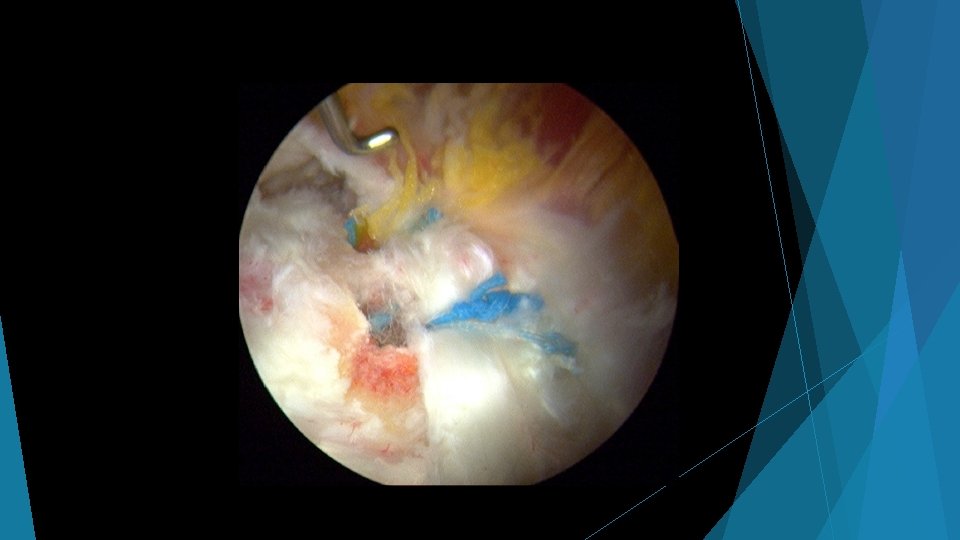

Hip Arthroscopy

Abductor repair surgery